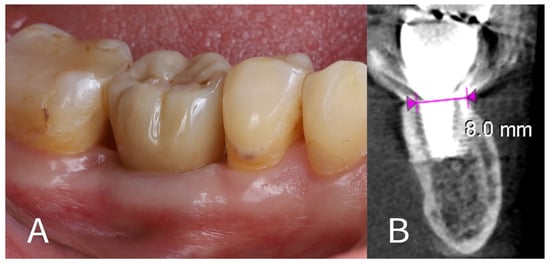

- Four-month assessment:

- Prosthetic rehabilitation: At approximately 4 months after the extraction and implant placement, the site was restored with a permanent prosthesis. A screw-retained monolithic full-contour zirconia crown (KATANA Zirconia™ YML, Kuraray Noritake Dental Inc., Tokyo, Japan) was fabricated and attached to the implant (Figure 8A). The crown was designed to have an emergence profile that matched the contour shaped by the healing abutment and surrounding tissue, thereby maintaining the ridge profile.

- One-year follow-up: The patient was re-examined again at 12 months post-implant placement (roughly 8 months after crown delivery). The patient reported excellent function with the implant and no discomfort. A final CBCT scan at 1 year showed that the alveolar ridge dimensions were unchanged from the 4-month scan (Figure 8B). The horizontal dimension of the buccal bone had an additional resorption of only ~0.1 mm between the 4-month and 12-month time points, indicating stable hard tissue conditions. The buccal plate remained intact and fully supported the implant. The peri-implant soft tissues were healthy, with no signs of recession or inflammation around the crown. The overall result at 1 year was a stable implant with well-preserved surrounding tissues, fulfilling both functional and aesthetic expectations for a posterior implant site.